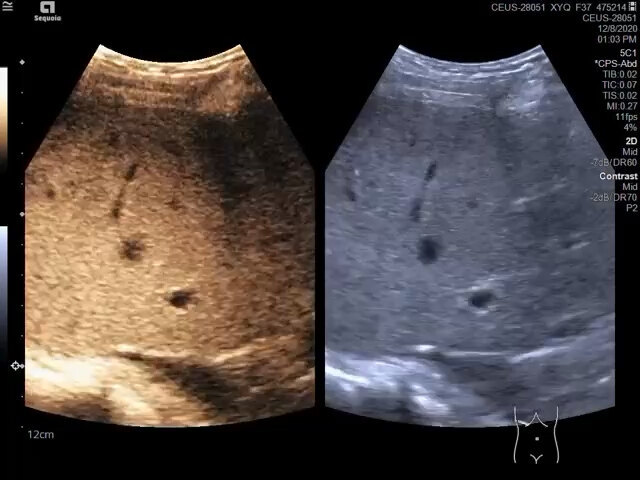

造影引導(dǎo)肝轉(zhuǎn)移瘤微波消融治療 常規(guī)超聲不能顯示的肝轉(zhuǎn)移瘤,在造影引導(dǎo)下進(jìn)行微波消融治療

鄒如海醫(yī)生的科普號(hào)2023年01月29日166

2